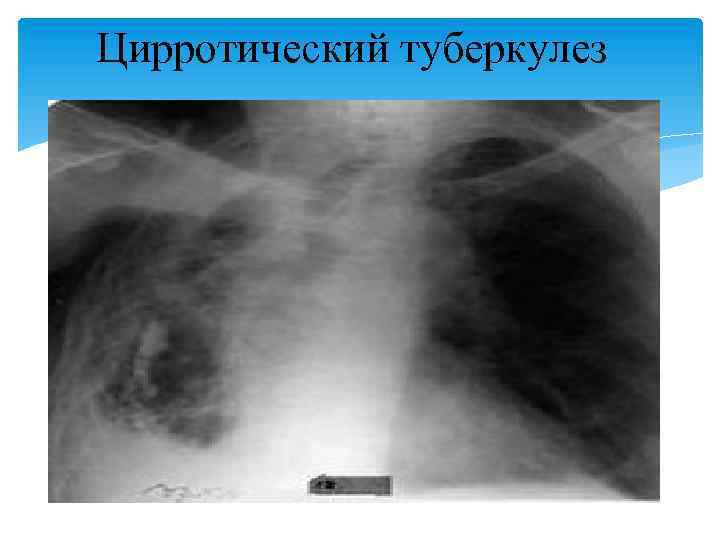

По мере затихания обострения симптомы интоксикации постепенно уменьшаются вплоть до полного исчезновения, исчезает или уменьшается кашель и выделение мокроты. При физикальном исследовании в области пораженной доли отмечается притупление жесткое, иногда бронхиальное, дыхание. Часто выслушиваются постоянные влажные мелкопузырчатые хрипы. Изредка бывает кровохарканье. В мокроте непостоянно выявляются МБТ, особенно при наличии полостных изменений. Рентгенологаческая диагностика. Рентгенологическая картина цирротического туберкулеза характеризуется большим полиморфизмом. Цирротические изменения в легких обычно четко отграничиваются от легочной ткани, наблюдается выраженное затенение патологического процесса с уплотнением плевры и смещением органов средостения в сторону цирроза. В легочной ткани имеются изменения туберкулезного характера в виде полиморфных очагов, рубцовых изменений, наличие одиночной или множественных туберкулем.

В непораженных участках и в контрлатеральном легком имеются признаки эмфиземы. Полостные изменения — бронхоэктазы, буллы, крупнокистозные и щелевидные образования, возможно являющиеся остаточными кавернами. Диагностика цирротического туберкулеза осуществляется по данным анамнеза и комплексного клинико-диагностического обследования. Дифференциальную диагностику проводят с цирротическими процессами другой этиологии. Лечение. Госпитализацию в стационар противотуберкулезного учреждения больных цирротическим туберкулезом легких проводят в период обострения. Лечебный и двигательный режим определяется состоянием больного; питание соответствует диете № 11. Химиотерапия носит строго индивидуальный характер и проводится в соответствии с данными о лекарственной устойчивости МБТ.